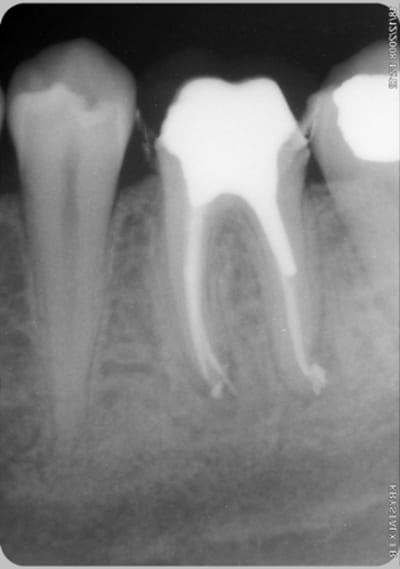

merci à ma petite chérie d'avoir passé du temps, supporté mes remontrances incessantes pendant le traitement, tenu bon quand lors du flair up post traitement je la suppliais d'extraire cette dent que je pensais condamnéé, et enfin d'avoir appliqué avec autant de rigueur les enseignements de Stéphane et Willy.

Moi j'ai ça, OK, c'est plus facile avec une prémolaire, mais je trouve la cicatrisation sympa.

1 an entre les 2 radios

le traitement a été fait cet été en juillet donc la rx post op 4 mois apres.

on a pas fait la couronne car en ce qui me concerne je pensais que la dent était condamnée et je m'attendait à devoir l'extraire lors d'une éventuelle poussée inflamatoire qui n'est jamais venue. Mais pour les autres cas je fais toujours comme ça inlay core pour étancheifier le plus vite possible et une provisoire pour attendre le résultat pendant 3 à 6 mois.